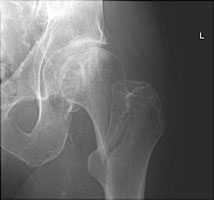

- Click on the image for a larger versionCJudet view of the right hip. Another example of an intertrochanteric fracture. This fracture is moderately displaced.